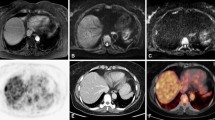

The visual evaluation demonstrated the colorectal tumours as FDG-accumulating lesions which were delineated with the highest contrast in the parametric images, reflecting the FDG phosphorylation (Fig. 1). In a few cases the delineation of the tumour was difficult on the normal FDG uptake images, while the parametric images clearly demonstrated the malignant lesion as a hypermetabolic area (Fig. 2). Overall, parametric imaging was helpful and supported the assessment of the PET studies. Generally, the images of the blood volume provided the delineation of the anatomy, while k 3-weighted images reflected the metabolised fraction of FDG.

Upper row: FDG PET examination of a patient with an adenocarcinoma of the colon. The SUV images reflect the tracer distribution 40–60 min following FDG administration. The images are scaled from 0 to 5 SUV. Middle row: the k 3-weighted images demonstrate trapping of FDG in the malignant lesion. The contrast is improved by parametric imaging. Lower row: images of the blood volume, which was not significantly enhanced in the tumour

Upper row: FDG PET images of a patient with an adenocarcinoma of the colon (right flexure). Low tracer uptake in the FDG images 40–60 min following FDG injection, which is nearly comparable to the tracer accumulation in the normal colon. Middle row: parametric images reflecting the trapping of FDG. The tumour is visible owing to the trapping of the tracer. Lower row: images of the distribution volume of the tracer. The distribution volume of FDG is equivalent or even higher in the normal colon as compared to the tumour; therefore detection of the tumour is hampered in the standard FDG uptake images